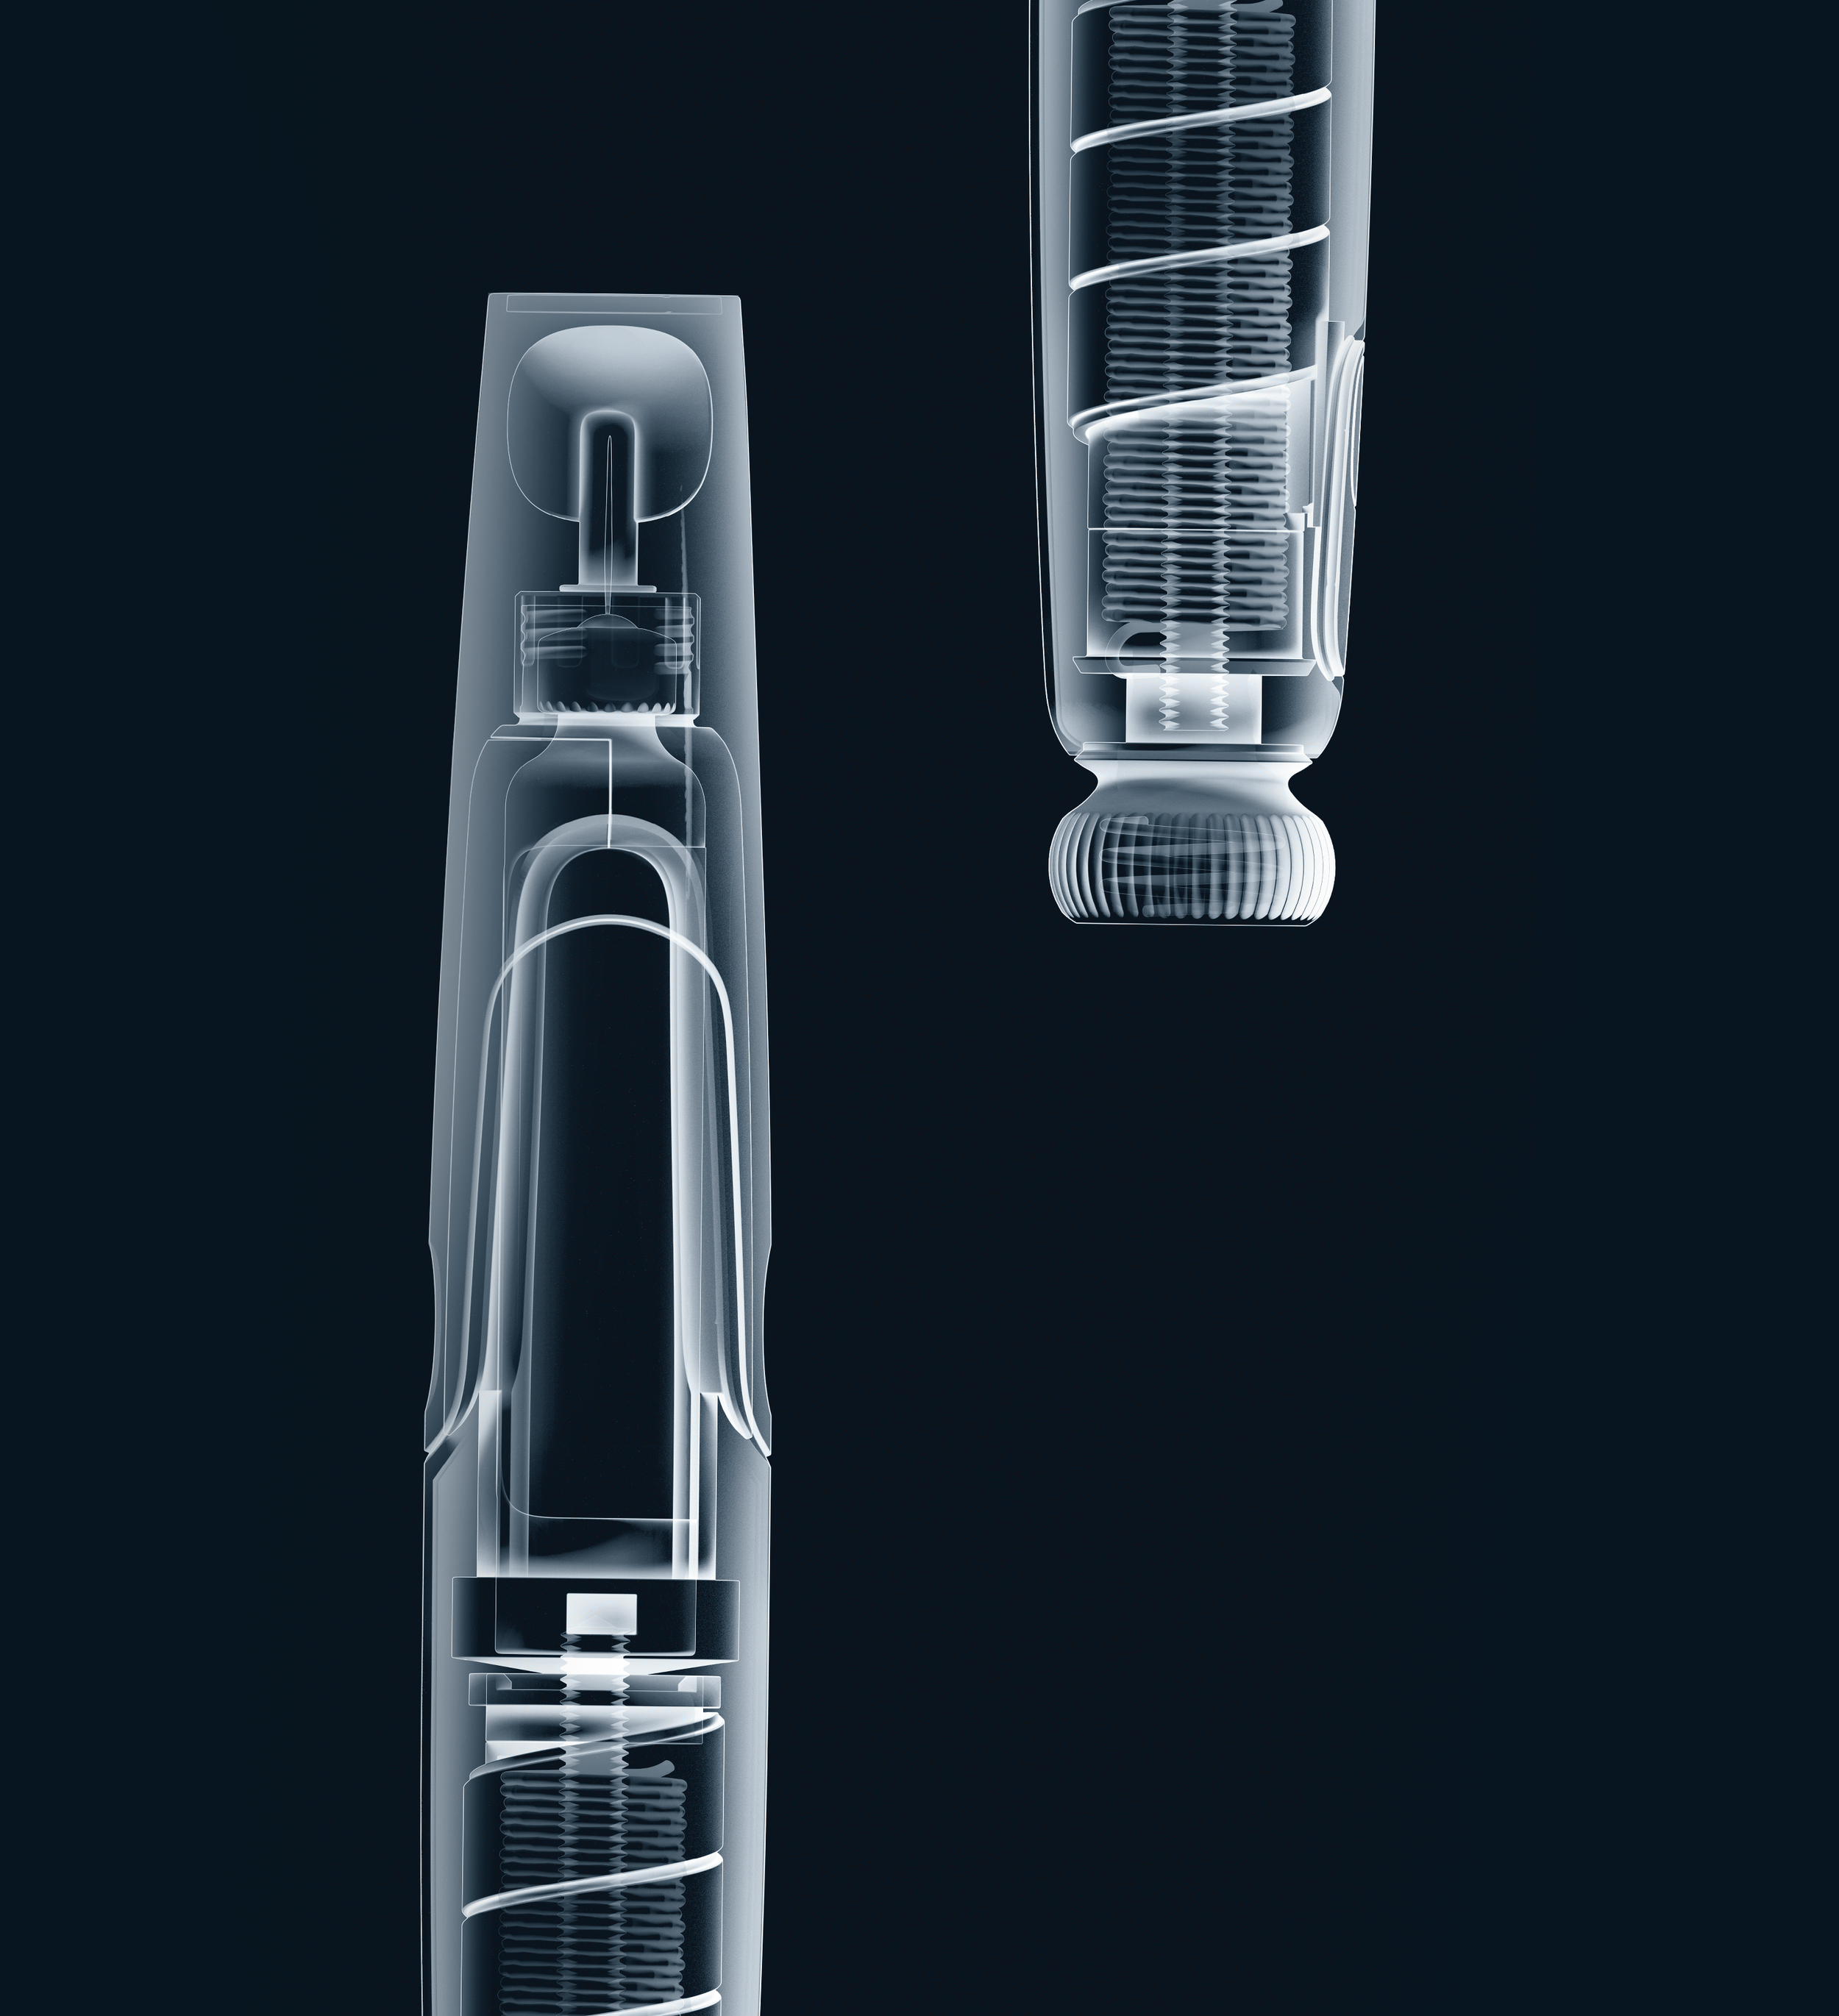

Bamboo is a reusable autoinjector that improves usability while reducing environmental impact. With fewer parts, optimized design, and innovative drive systems, it saves space, energy, and costs, addressing the medical industry’s sustainability challenges. (Cambridge Consultants)